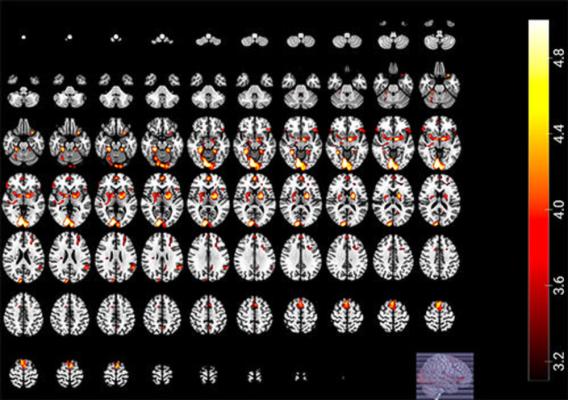

All participants were presented with a compilation of matches containing 63 goals. While the participants viewed the match compilation, their brain activity was measured using fMRI, a noninvasive imaging technique that detects changes in the brain's blood flow.

The fMRI results showed that brain activity changed when the fan's team succeeded or failed.

"When their team wins, the reward system in the brain is activated," Dr. Zamorano said. "When they lose, the mentalization network can be activated, taking the fan to an introspective state. This may mitigate some of the pain of the loss. We also observed inhibition of the brain hub that connects the limbic system with frontal cortices, hampering the mechanism that regulates cognitive control and increasing the probability to fall into disruptive or violent behavior."